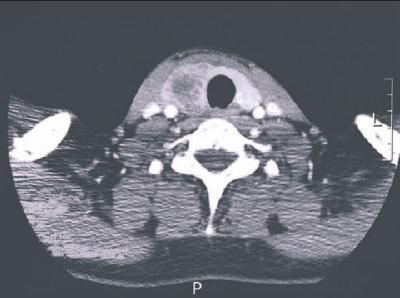

Radiological examination revealed cystic lesions of the thyroid gland with decreased enhancement; a thyroid abscess was therefore suspected (day 3; Figure 1). No pyriform sinus fistula (PSF) was detected by laryngoscopy or CT. Because the blood culture grew methicillin-sensitive Staphylococcus aureus (MSSA), cefazolin was added to the therapeutic regimen. Despite this antibiotic therapy and ultrasonography-guided aspiration (day 6; Figures 2 and 3), the patient's condition did not improve. Surgery was performed to manage the thyroid abscess (day 8).

This neck CT scan shows a cystic lesion of the thyroid gland with decreased enhancement.